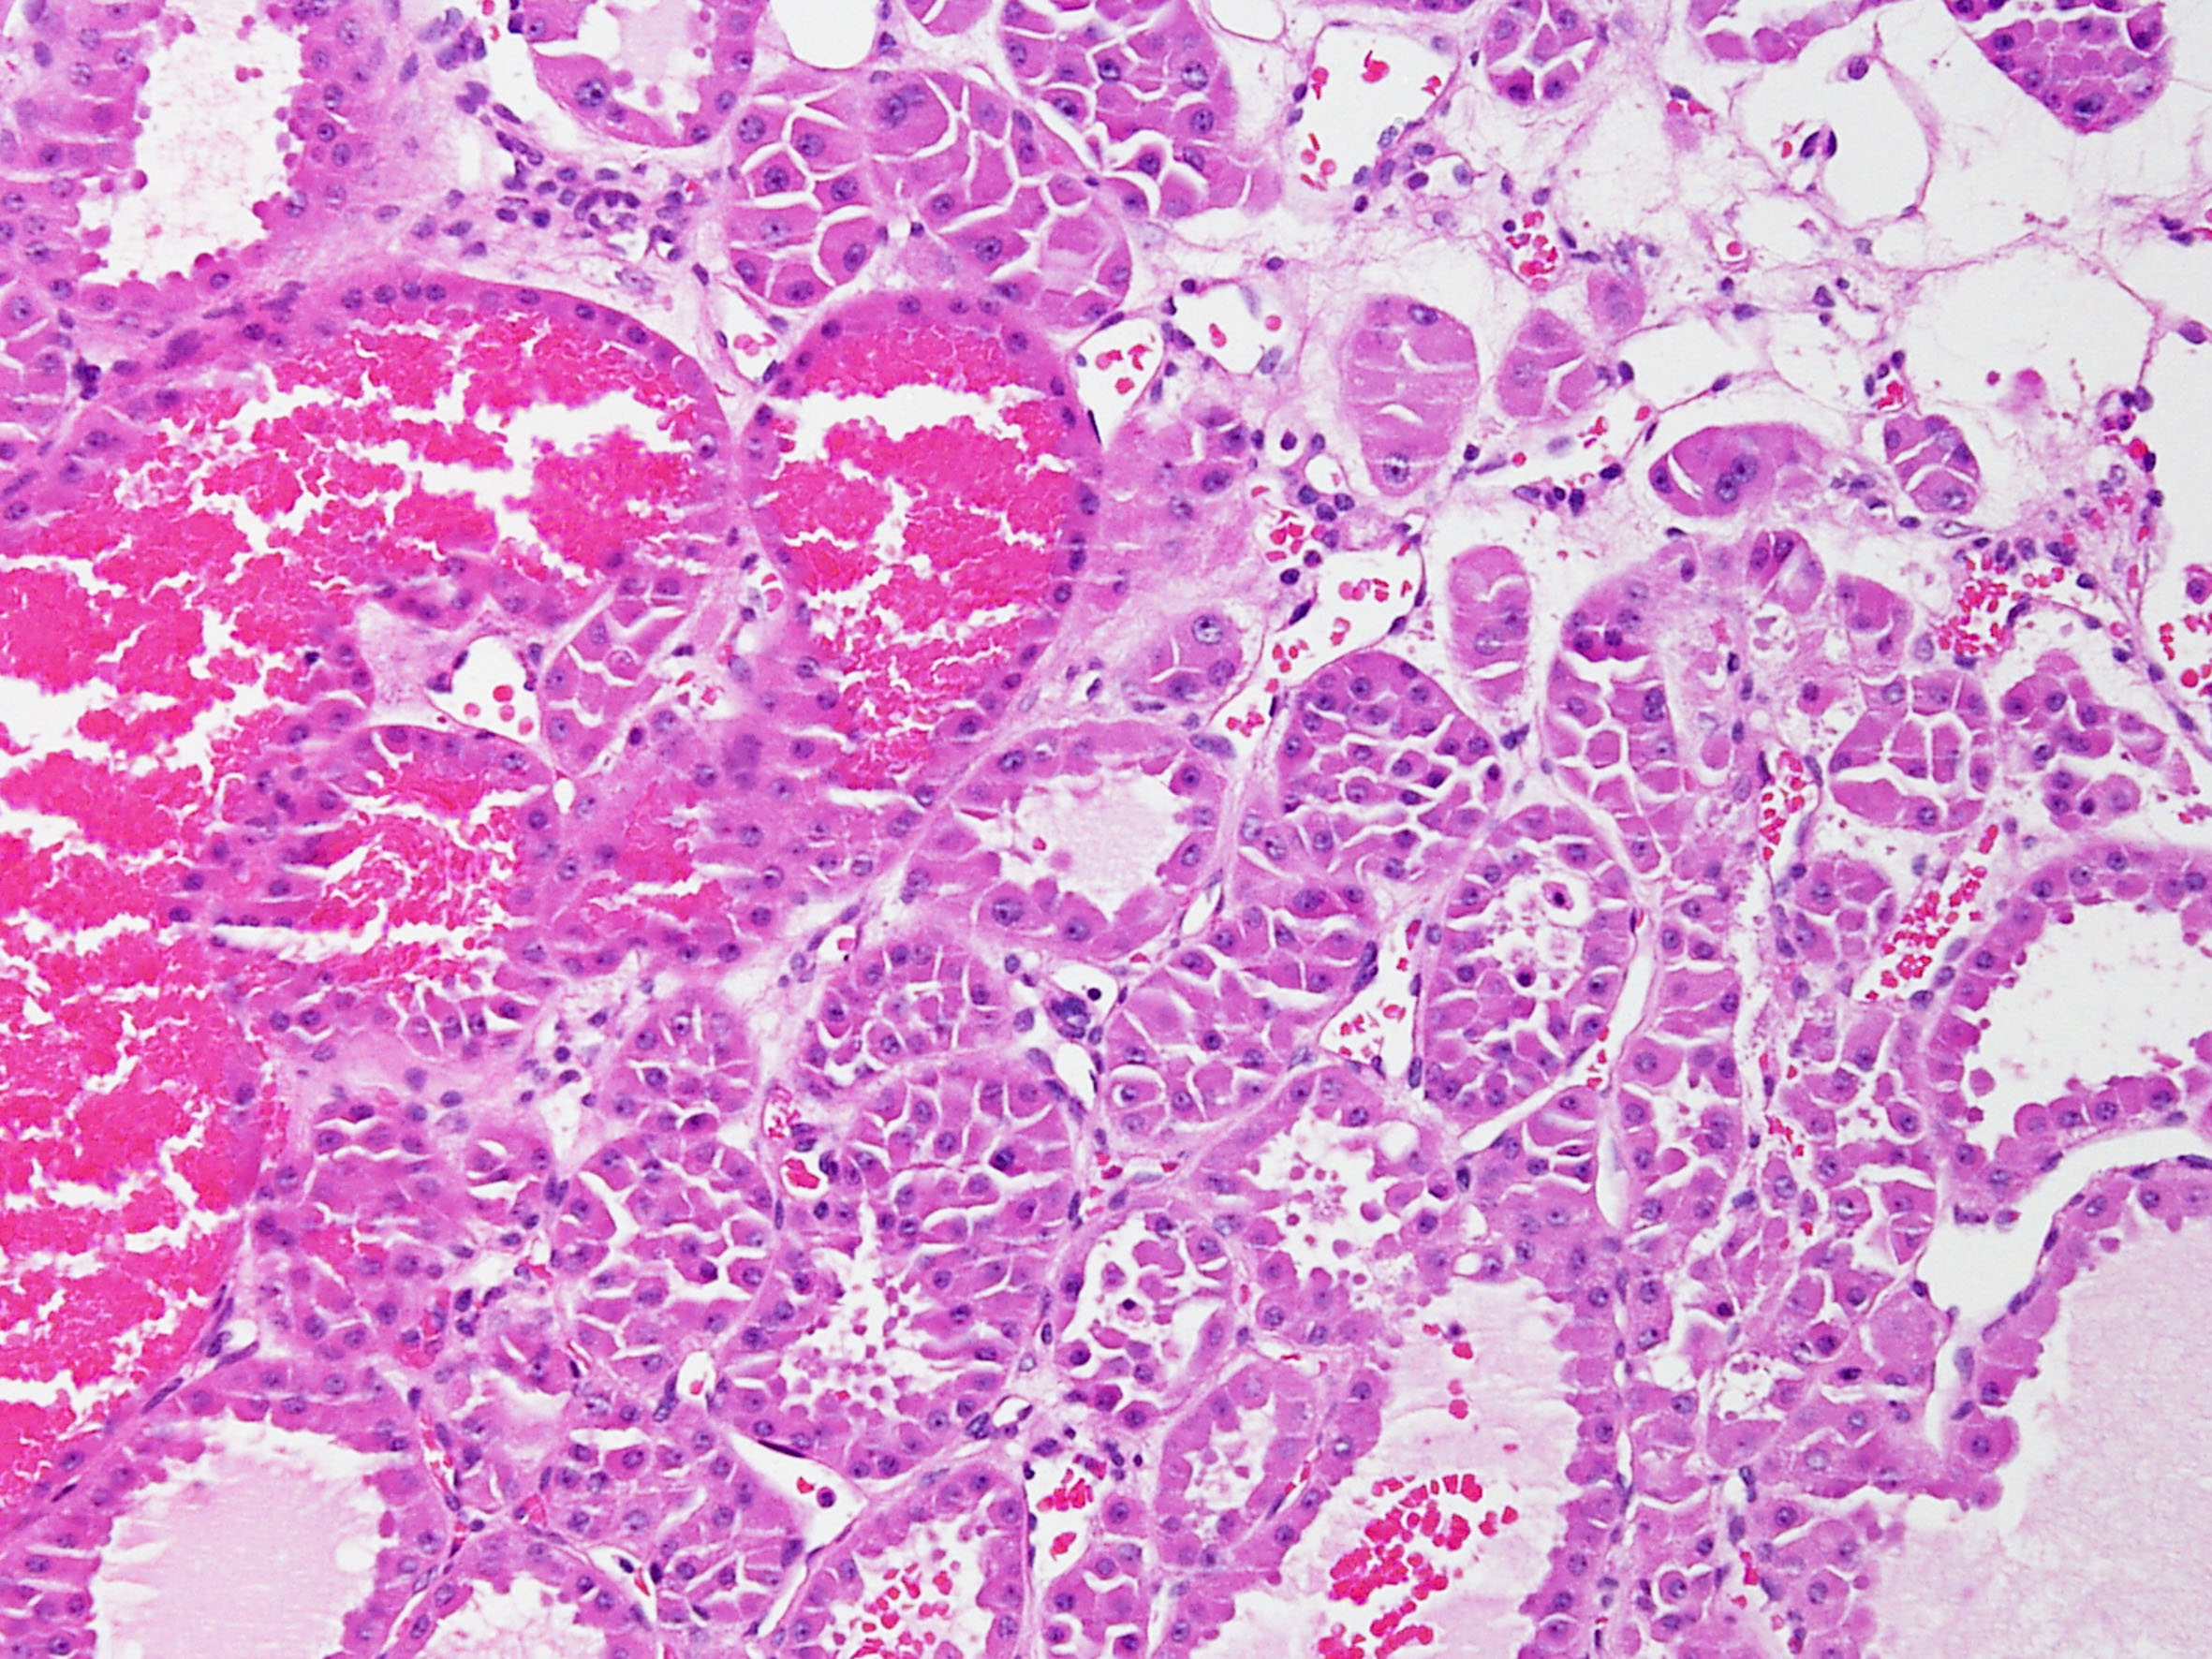

Consensus grade: oncocytoma

Case description (by case creator):

Oncocytoma